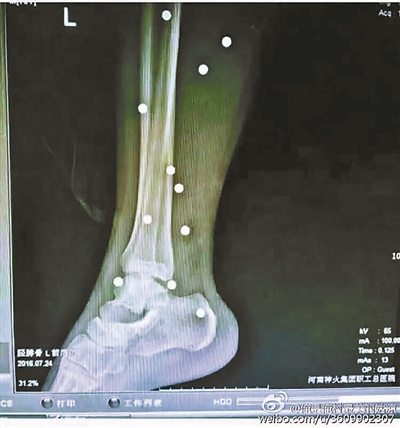

傷者體內(nèi)取出的鋼珠

爆炸導(dǎo)致鋼珠遍布傷者身體各處

黃明的伯伯對北青報記者表示,由于黃明直接踩到了爆炸物,所以傷情最為嚴重,“他的腿被炸斷,身體內(nèi)被炸進了40多顆鋼珠。手術(shù)后已經(jīng)從體內(nèi)取出29顆鋼珠,還有十多顆鋼珠沒有取出來?!备鶕?jù)黃明的入院記錄,他全身有多處爆炸傷,且全身多處異物存留。

爆炸發(fā)生時,陳浩的位置與黃明靠得很近,因此也受傷較重。他告訴北青報記者,經(jīng)過10多個小時的手術(shù)后,醫(yī)生從他身體里取出了12顆鋼珠。目前,他和黃明兩人經(jīng)過手術(shù)后,已從重癥監(jiān)護室轉(zhuǎn)至普通病房。其余三人中,陳剛的臀部受傷,當天晚上在醫(yī)院清理完傷口后便回了家,而同行的兩名女生身上有一些擦傷。